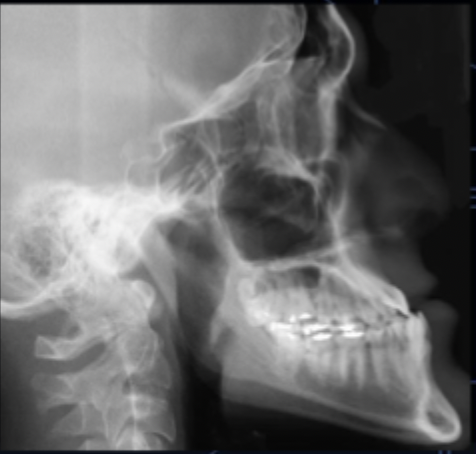

<p>what class of occlusion is shown in this x-ray? </p>

what class of occlusion is shown in this x-ray?

class II (x-ray)